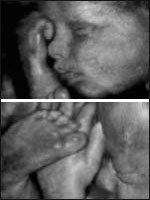

Ved hjælp af den nyeste teknologi er det muligt at danne tredimensionale ultralydbilleder af fostret. Når 3D vises live, opstår der 4D billeder. De bedste 3D/4D billeder opnås i 18.-24. graviditetsuge. På dette tidspunkt kan man foretage en gennemscanning af fostret.

Der foretages en grundig gennemgang af hoved, ryg, hjerte, nyrer, mavesæk, urinblære og arme/ben.